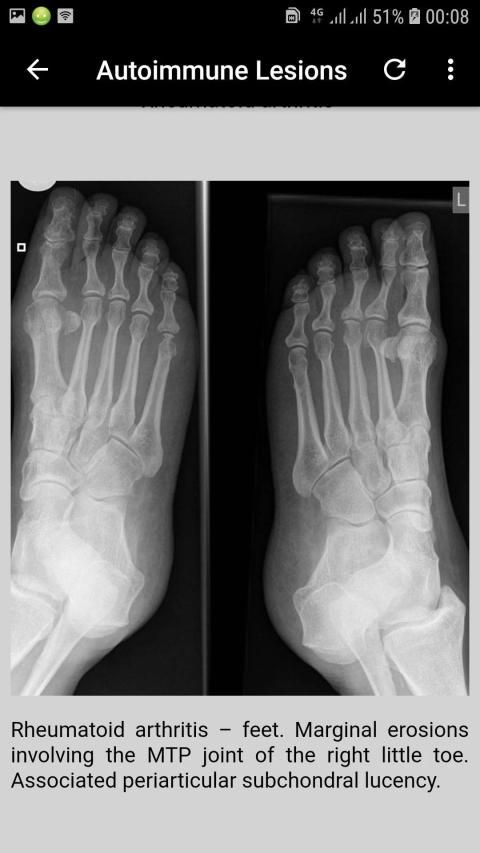

2 views

In the context of trauma at least 2 views of the body part in question are usually required. If looking for specific disease entities, for example erosions in rheumatoid arthritis, this may be less important. In some cases, such as possible scaphoid injury, more than 2 images are required.2 views are better than 1